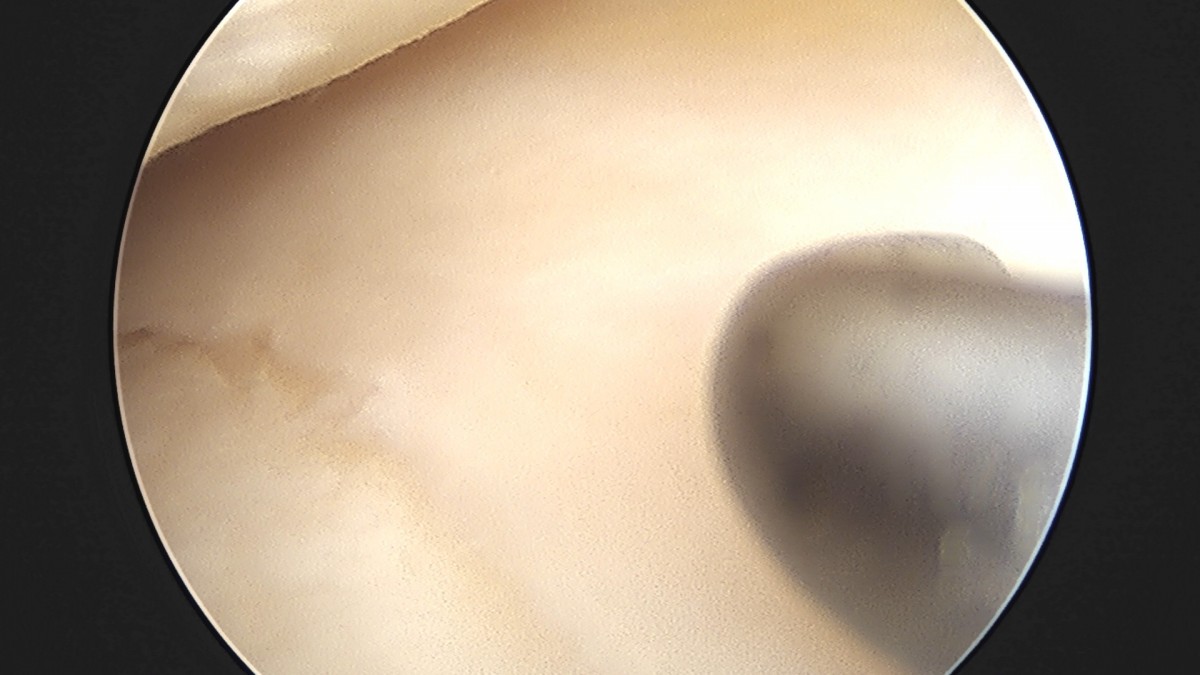

이재상원장님 무릎 반월상 연골판 절제술 소영O 환자

작성자 최고관리자 댓글 0건 조회 715회 작성일 25-09-16 15:45